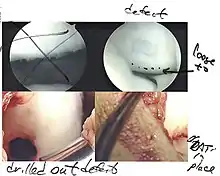

Arthroscopic image of OATS surgery on the medial femoral condyle of the knee

The choice of surgical versus non-surgical treatments for osteochondritis dissecans is controversial.[51] Consequently, the type and extent of surgery necessary varies based on patient age, severity of the lesion, and personal bias of the treating surgeon—entailing an exhaustive list of suggested treatments. A variety of surgical options exist for the treatment of persistently symptomatic, intact, partially detached, and completely detached OCD lesions. Post-surgery reparative cartilage is inferior to healthy hyaline cartilage in glycosaminoglycan concentration, histological, and immunohistochemical appearance.[52] As a result, surgery is often avoided if non-operative treatment is viable.

Intact lesions

If non-surgical measures are unsuccessful, drilling may be considered to stimulate healing of the subchondral bone. Arthroscopic drilling may be performed by using an antegrade (from the front) approach from the joint space through the articular cartilage, or by using a retrograde (from behind) approach through the bone outside of the joint to avoid penetration of the articular cartilage. This has proven successful with positive results at one-year follow-up with antegrade drilling in nine out of eleven teenagers with the juvenile form of OCD,[53] and in 18 of 20 skeletally immature people (follow-up of five years) who had failed prior conservative programs.[54]

Hinged lesions

Pins and screws can be used to secure flap (sometimes referred to as hinged) lesions.[55] Bone pegs, metallic pins and screws, and other bioresorbable screws may be used to secure these types of lesions.[56]